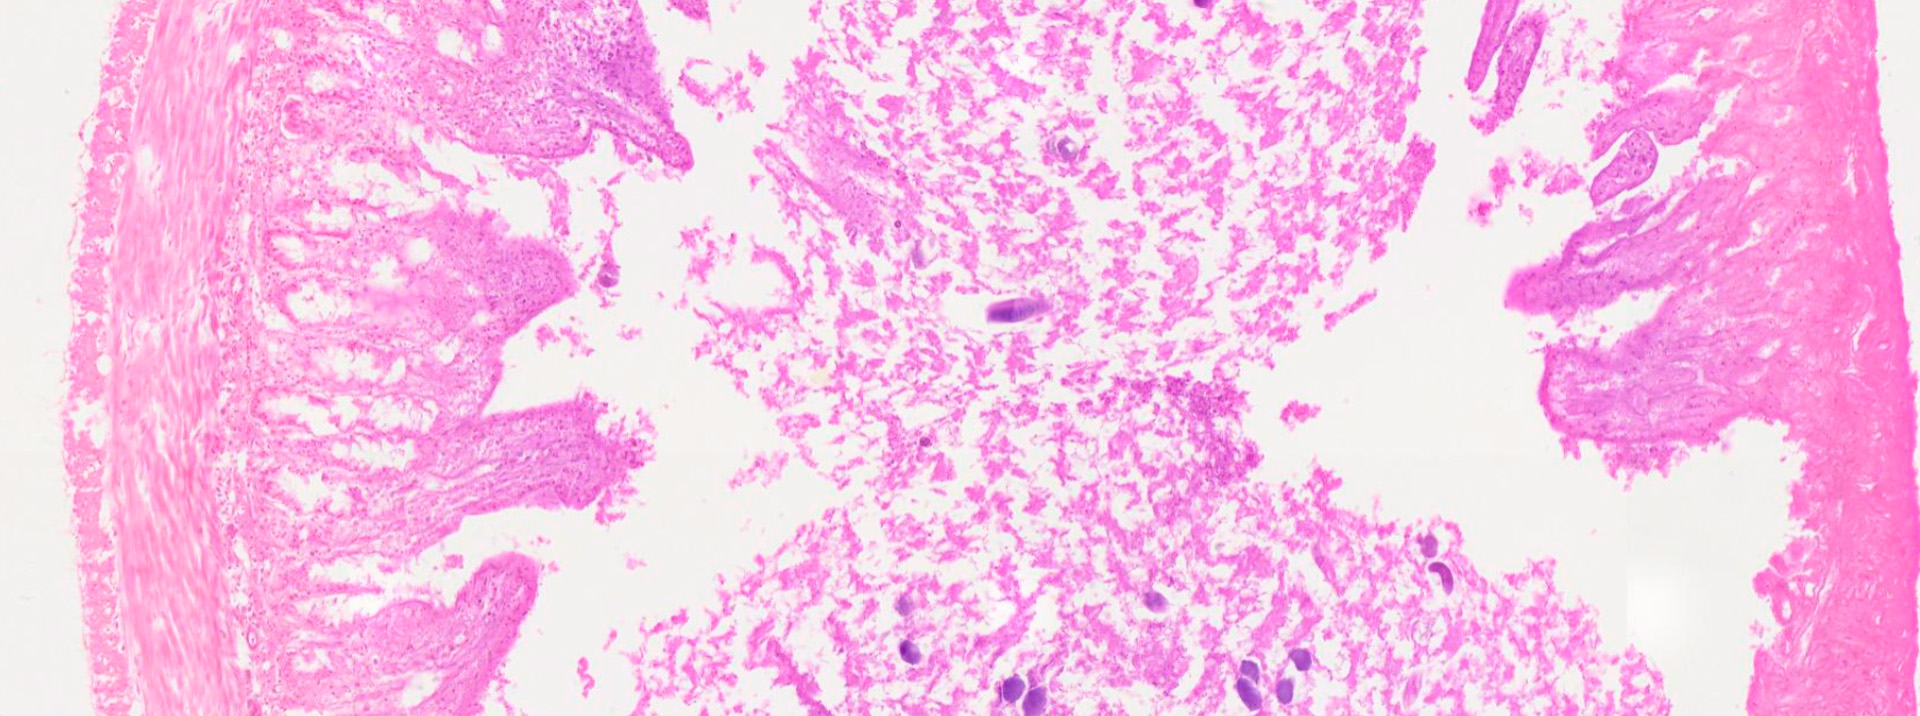

IMAGEN ESCANEADA

Enterobius vermicularis en Apéndice

https://pathpresenter.net/public/display?token=3c862eda

UBICACIÓN: Adultos en el ciego y apéndice cecal. Hembras grávidas y huevos en la región perianal y perineal.

CARACTERÍSTICAS: Nematodo fusiforme de color blanquecino, conocido comúnmente como “pidulle” u oxiuro. Presenta un marcado dimorfismo sexual. El ciclo de vida es directo (monoxeno) y no requiere paso por la tierra.

• Hembra Adulta: Mide 8–13 mm x 0.3–0.5 mm. Su extremo posterior es recto y muy aguzado (alfiler, de ahí el término pinworm). Tras la cópula en el ciego, migra grávida (con el útero distendido por miles de huevos) a través del ano, generalmente durante la noche, para oviponer en los márgenes perianales.